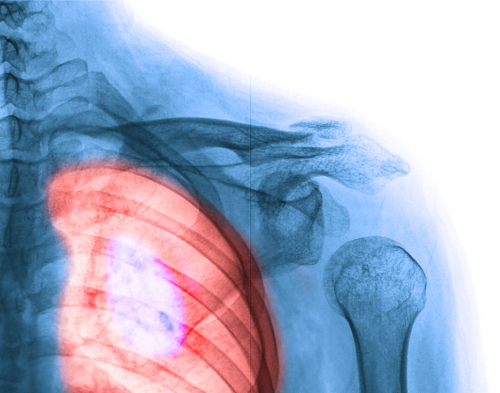

1. Le cancer du sein

Le cancer du sein est, sans aucun doute, celui qui a une plus grande incidence sur les femmes. Cependant, il faut signaler que c’est celui qu’on soigne le plus facilement.

Il est possible aussi que nous ayez perdu un être cher à cause de cette terrible maladie. Mais la science avance et, aujourd’hui, les femmes qui survivent à un cancer du sein sont de plus en plus nombreuses.

L’auto-exploration et les mammographies sont des facteurs clés pour sa détection précoce. Ici, nous vous donnons des signes et des symptômes dont vous devez tenir compte :